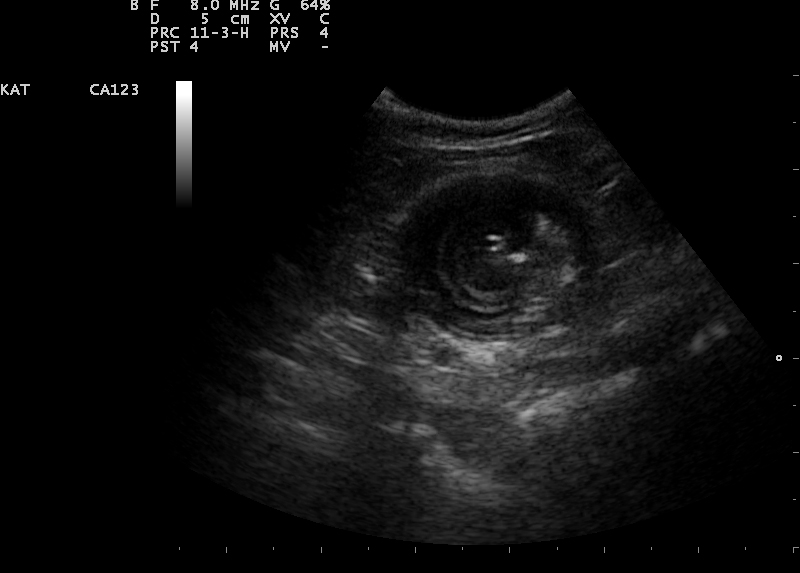

Een echo is het duidelijkst om een invaginatie te zien. Wanneer een invaginatie permanent is, zal deze met de echo meestal goed zichtbaar zijn. Echter wanneer het een temporel invaginatie is, kan dit heel lastig zijn. Een temporele invaginatie is een invaginatie die het ene moment er is en het andere moment niet. Deze invaginaties belemmeren meestal de passage maar sluiten het niet geheel af.